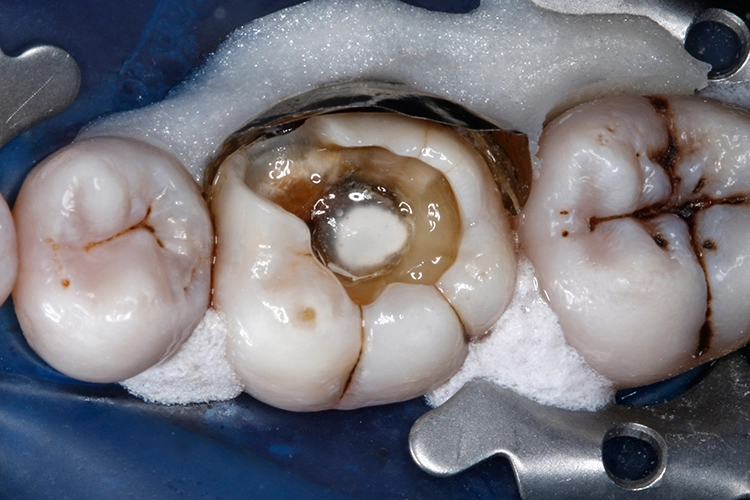

Ein 38-jähriger Patient erschien in unserer Sprechstunde mit einem frakturierten mesiolingualen Höcker neben einer okklusalen Amalgamfüllung am unteren rechten 1. Molaren (Zahn 46). Der Vorfall hatte sich bereits vor einer Woche ereignet, der Zahn war noch am selben Tag im zahnärztlichen Notdienst provisorisch mit einer Glasionomerzementfüllung versorgt worden (Abb. 1). Der Defekt erstreckte sich bis auf Höhe der marginalen Gingiva (Abb. 2).

Anschließend wurden sämtliche Kavitätenränder mit einem Feinkorndiamanten nachgearbeitet und finiert. Danach wurden die pulpanahen Kavitätenareale mit einem selbstlimitierenden Polymer-Rosenbohrer (Polybur, Gebr. Brasseler GmbH & Co. KG, Lemgo) substanzschonend exkaviert (Abb. 7), eine Exposition der Pulpa konnte mit diesem Vorgehen der selektiven Exkavation vermieden werden (Abb. 8) [51–55]. Das pulpanahe Dentin im Zentrum der Kavität wurde mit einer dünnen Schicht röntgenopaker Calciumhydroxidpaste auf wässriger Basis (Calcicur, VOCO) indirekt überkappt (Abb. 9). Das Calciumhydroxidpräparat wurde mit einer partiellen Unterfüllung aus lichthärtendem kunststoffmodifiziertem Glasionomerzement (Ionoseal, VOCO) abgedeckt (Abb. 10).